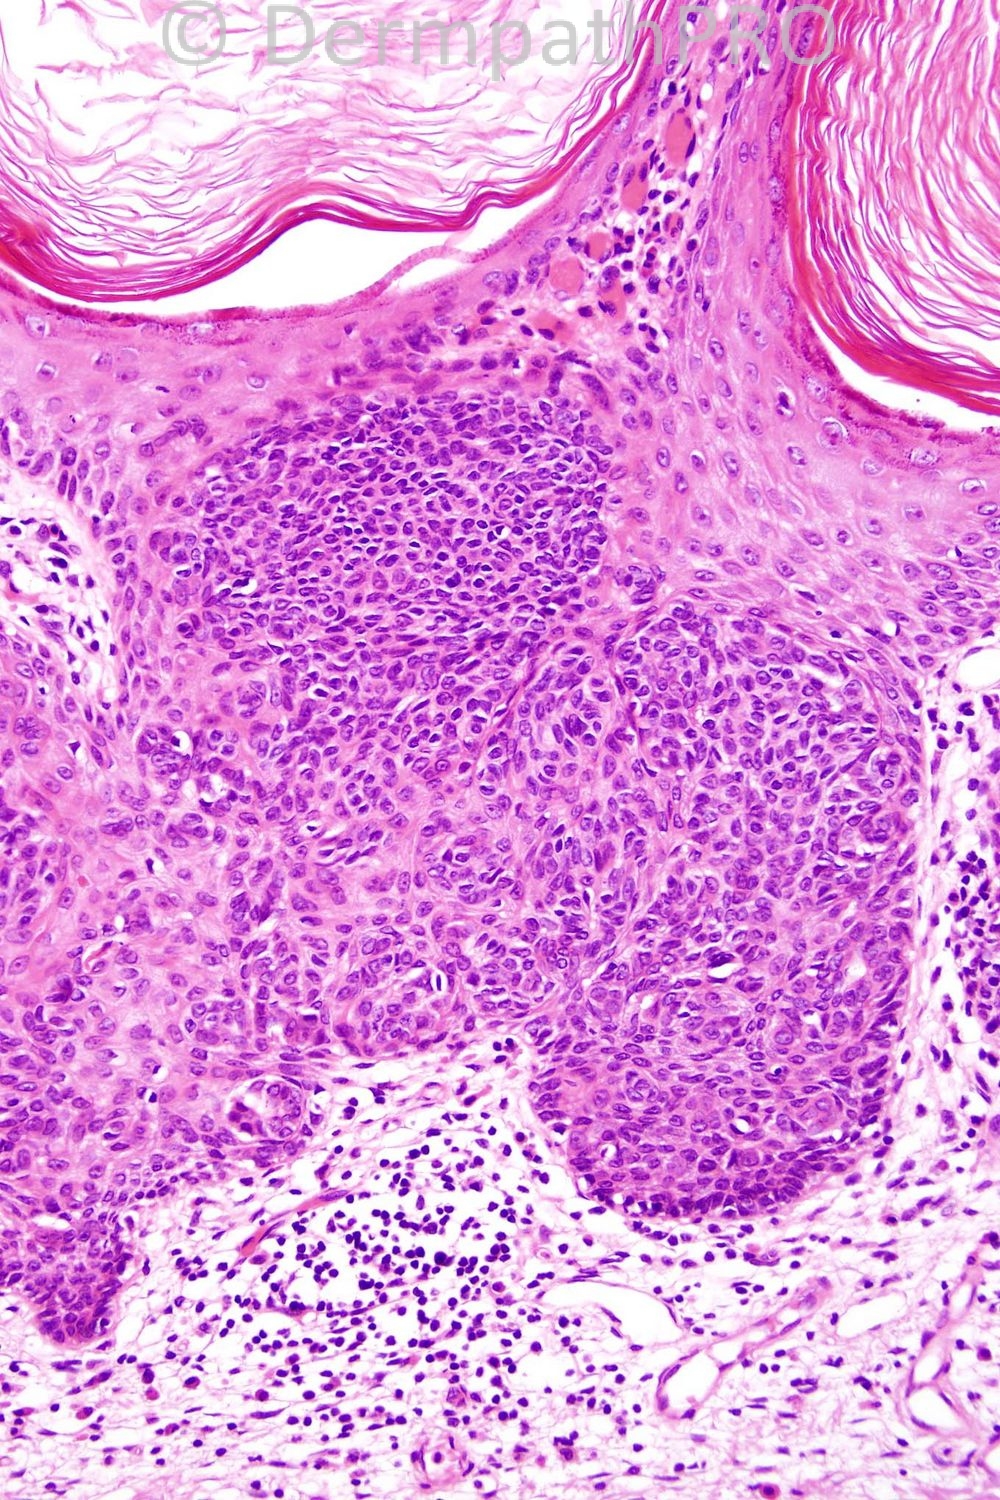

Female 36 years, plaque on lower leg.

Very good comments. I agree that there is a definite poroid look to the cells and a clonal population is evident. Ductal differentiation was evident elsewhere in this lesion. I diagnosed it as hidroacanthoma simplex.

Beautifully demonstrated Borst Jadasson Phenomenon.. Clonal Seb K vs. Hidroacanthoma simplex... Lovely,,,

Hidroacantoma simplex (intra-epidermal poroma). The cells look "poroid" as opposed to the clear nests in clonal seborrhoeic keratosis or the atypical nests in nested Bowen's disease.

clonal seborrheic keratosis (Borst Jadassohn phenomenon) vs hidroacantoma simplex (there is no ductal differentiation)